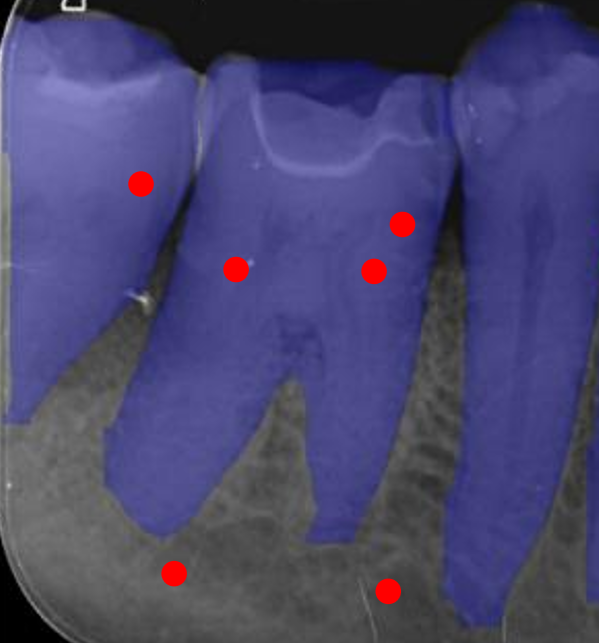

We conducted comprehensive annotation of the collected radiographs, divided into four steps. These include annotating Bone Level Keypoints (BLK) for each tooth, identifying the Teeth Bounding Box (TBB) with tooth orientation, annotating ARR keypoints, and widened PLS bounding boxes. Figure 1 provides visual examples of the annotations.

Refer to caption

Figure 1: Three images containing example annotations of the collected keypoints and rotating bounding boxes.